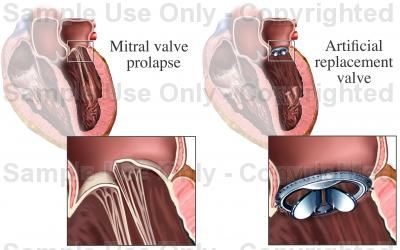

Másrészt, hogy diagnosztizálni PATOLÓGIAI mitrális prolapsus, süllyedés a szórólapok kell két kiálló részek és a patológiai öklendezés MK (azaz mérsékelt vagy jelentős mértékben).

És ez a leírása egy szelep áthelyezésére egy mesterséges szeleppel:

2. A szelepek KÖZPONTJÁNAK elcsúszása nagyon távoli kapcsolatban áll az elöregedéssel.

Tisztelt kollégák, Kérjük, adja ki a Pathologic prolapse MK hordozójának büszke címet csak azoknak, akik valóban megérdemlik.